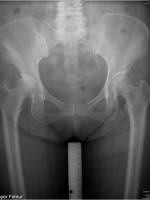

CroweIII-IV的先髋常见的粗隆下截骨术:

1) 先在X光片上测量需拉下股骨头旋转中心的距离,并在术中判断软组织松解后,是否可拉下此距离,此距离就是粗隆下截骨大约的高度(黄线)。

2) 股骨锉至最适合的大小,并在远端使用较小的股骨钻多钻100px。

3) 打入相对应的股骨假体。

4) 测量需拉下股骨的距离,达到重建髋臼的旋转中心,并和术前计划比较。

5) 在小转子下截骨,并尽量接近需拉下的距离。

6) 将股骨复位拉下,并使截骨后的股骨两侧,靠假体尽量靠近到闭合,若需要增强假体固定,可以在截骨线的上下两端,使用钢缆环扎增强假体稳定。

7) 若截骨处无法闭合,可使用自体移植骨(截骨块)增加固定和骨生长的效果。